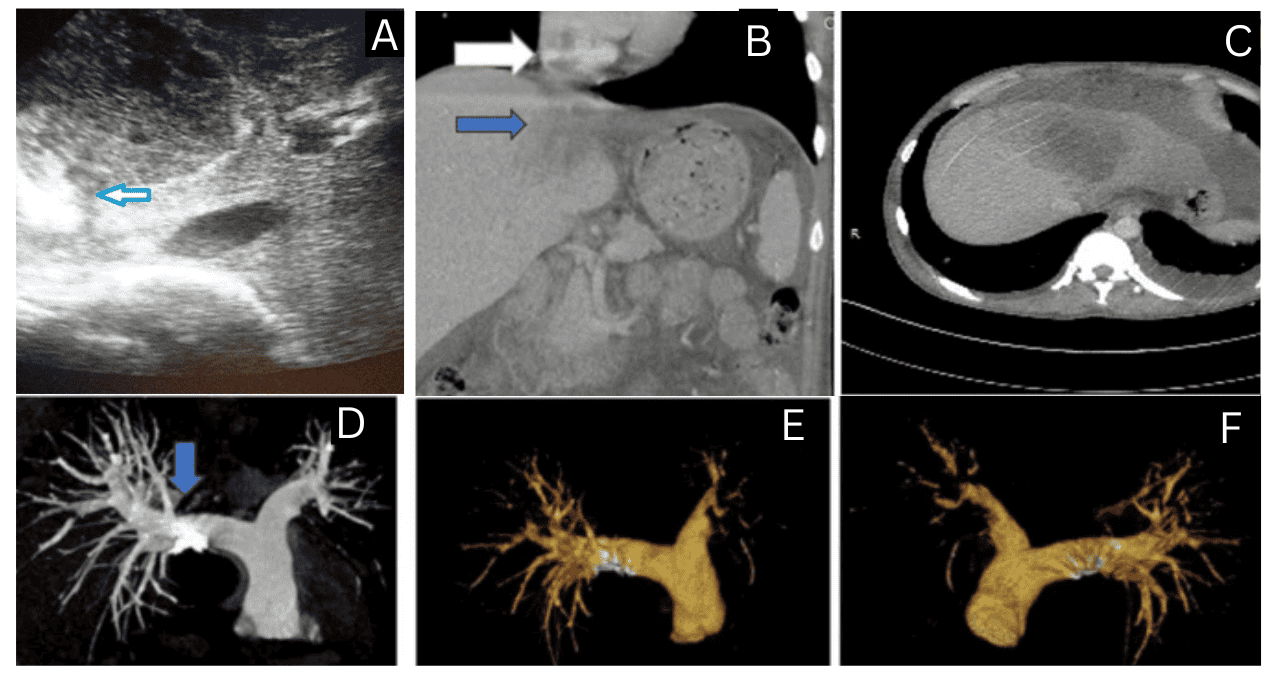

Un caso de ruptura de absceso amébico en la vena cava inferior, con un trombo que se extiende hasta la aurícula derecha y tromboembolismo pulmonar tratado con éxito.